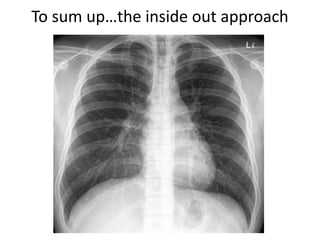

To sum up…the inside out approach